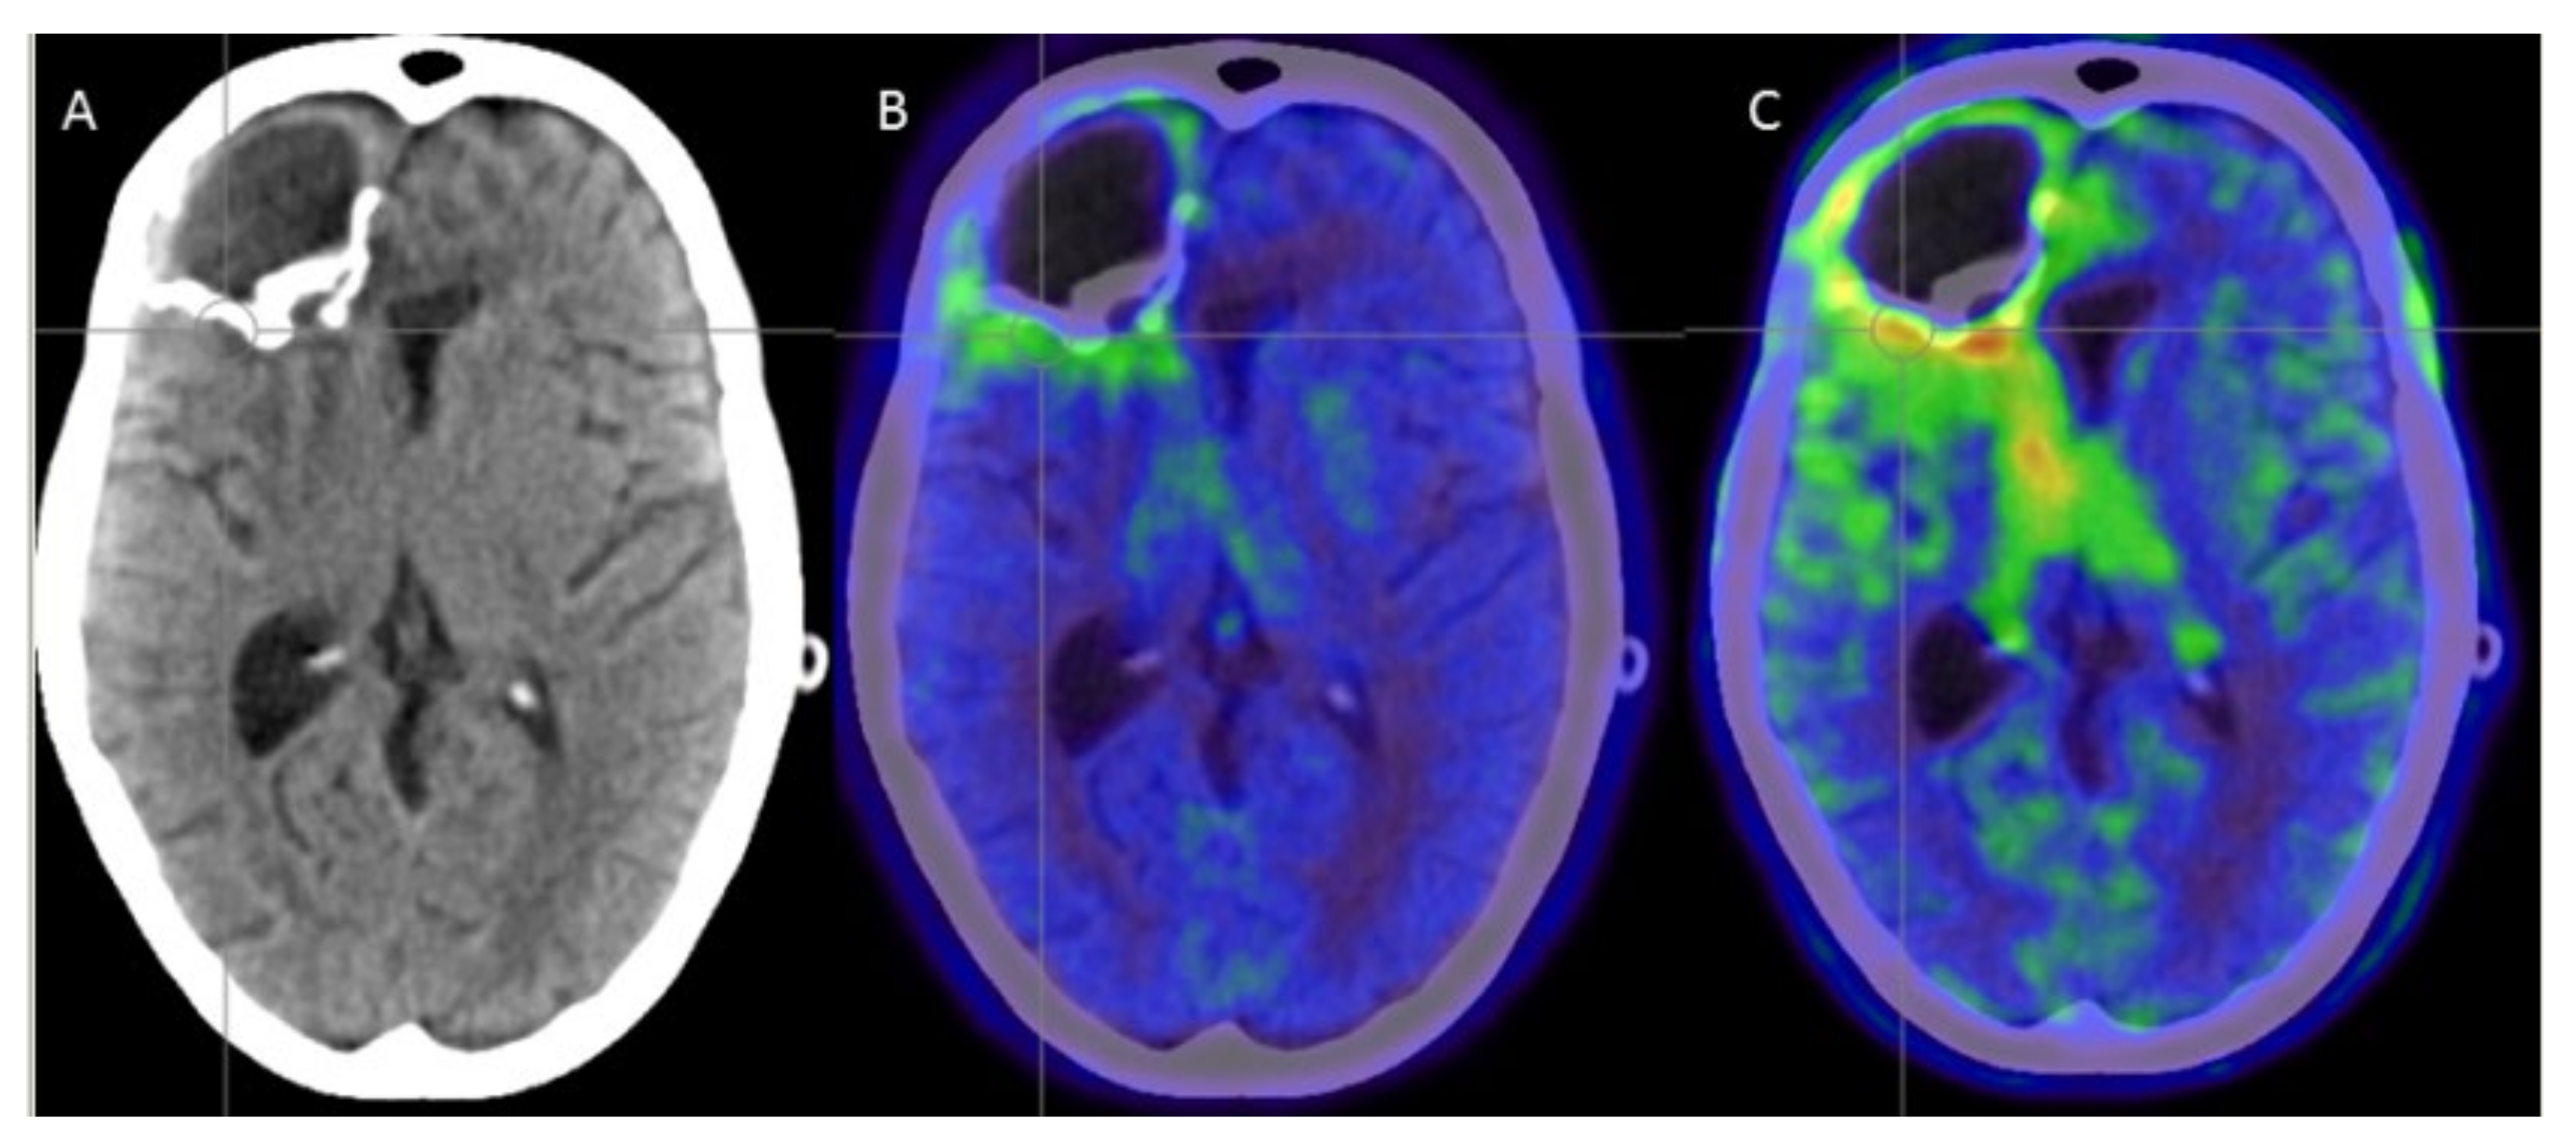

3.2. Safety and Complications